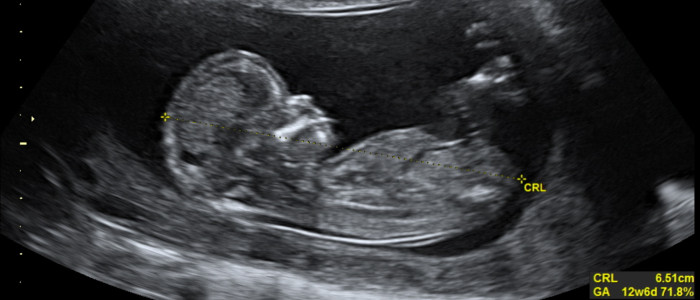

При неймовірно похмурому повороті подій дослідники виявили мікропластик у людській плаценті й навіть у новонароджених.

Команда опублікувала статтю про свої висновки у журналі Environmental Health Perspectives. У ході дослідження вони виявили, що практично неможливо запобігти проковтуванню та поглинанню мікропластику дітьми та немовлятами навіть до їх народження.